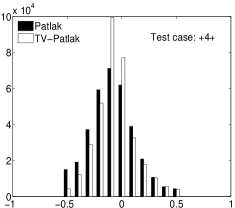

In the images shown in the figures we illustrate the calculated uptake rates of the FDG. Images for the CMRGlc can be obtained by directly scaling . In figure 1 we compare the result of using Patlak and TV-Patlak for estimating the uptake rates with respect to no noise, noise in the input function, Poisson noise in the sinogram, and finally with respect to the case in which the irreversibility assumption is violated but without noise in the sinogram or input data. In each case the histogram of the relative errors is given on the left, the Patlak image in the middle and the TV-Patlak on the right. The different scales in the histograms are due to the total number of results illustrated. When there is no noise (triples and ) the histogram illustrates results over all voxels but only one simulation, while for the noisy simulations the results are for all voxels over all realizations of the noise. The TV-Patlak images are more homogeneous in all cases and the relative errors are smaller. The figures clearly show the improvements of employing the TV-Patlak method as compared to using Patlak independently for each voxel. This is confirmed in figure 2 in which images with noise in the sinogram, positive and different noise levels in the input function are shown.